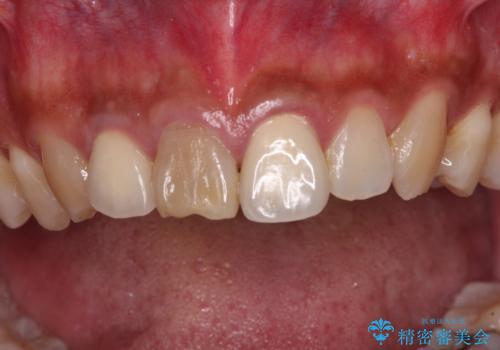

時間の経過とともに、セラミックにしなかった当該歯の変色が目立つようになり、オールセラミッククラウンにて補綴することとしました。

変色した歯はきれいになり、両隣の歯とも自然に馴染み、ご家族からも好評で大変満足されました。